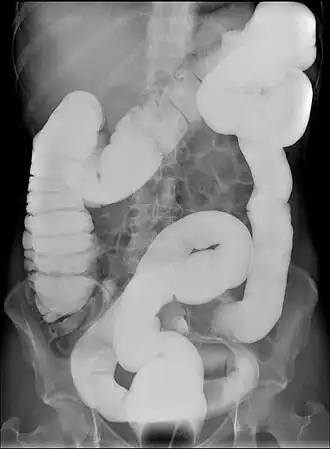

Долихоколон ( др.-греч. δολιχός «длинный» и др.-греч. κόλον «толстая кишка»)— аномалия развития кишечника, удлинение одного из отделов или всей ободочной кишки. Имеет клиническое значение — может приводить к болям в животе и запорам. Является самой частой аномалией развития толстой кишки.

Первичная диагностика проводится с помощью пальпации ободочной кишки. Для точного диагноза используют колоноскопию или ирригоскопию. Рентгеноконтрастные маркеры позволяют оценить патологию моторной функции кишки. Виртуальная компьютерная колонография может быть альтернативой ирригоскопии[2]. При диагностировании следует исключить мегаколон и болезнь Гиршпрунга, которые также вызывают запоры[1]. Так же необходимо исключить воспалительные заболевания кишечника, ишемический колит, новообразования толстой кишки и медикаментозный запор[2].